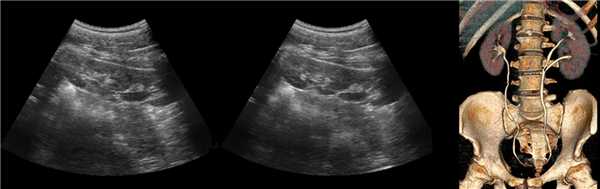

Аплазия левой почки

Удвоенная почка без признаков обструкции

На УЗИ можно выявить опущение почки (нефроптоз) или нетипичную локализацию органа (дистопия), вплоть до расположения в малом тазу.